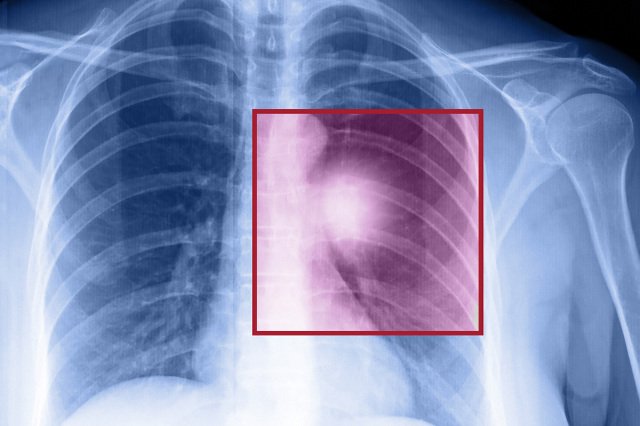

W ciągu najbliższych 35 lat Wielka Brytania może niemalże całkowicie wyeliminować problem „nowotworowych zgonów”, które występują u pacjentów mających mniej niż 80 lat. Do takiego wniosku doszli naukowcy z University College London i King's College London. – Nowotwory stają się powoli albo możliwe do uniknięcia, albo uleczalne – powiedział prof. David Taylor z University College London.

Dane statystyczne pokazują, że w ciągu ostatnich 25 lat śmiertelność wśród brytyjskich pacjentów, u których zdiagnozowano nowotwór, systematycznie spadała. Wpływ miało na to kilka czynników: malejąca liczba palaczy, poprawa procesu diagnozowania chorób oraz ulepszenie metod leczenia chirurgicznego, radiologicznego i farmakologicznego.

Jeśli dalszy postęp medycyny będzie postępował równie szybko, a brytyjski National Health Service będzie mógł przeznaczać na leczenie onkologiczne odpowiednie środki, to do 2050 roku zgony spowodowane przez nowotwory staną się rzadkością wśród pacjentów mających mniej niż 80 lat. Tak sugeruje opublikowana właśnie analiza.